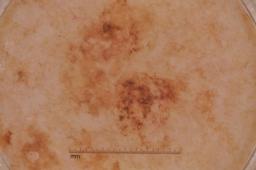

MSK-4

- Name: MSK-4

Description:

Images found based on a search for patients with a personal history, clinical diagnosis, or differential diagnosis of melanoma. All diagnoses confirmed by histopathology.